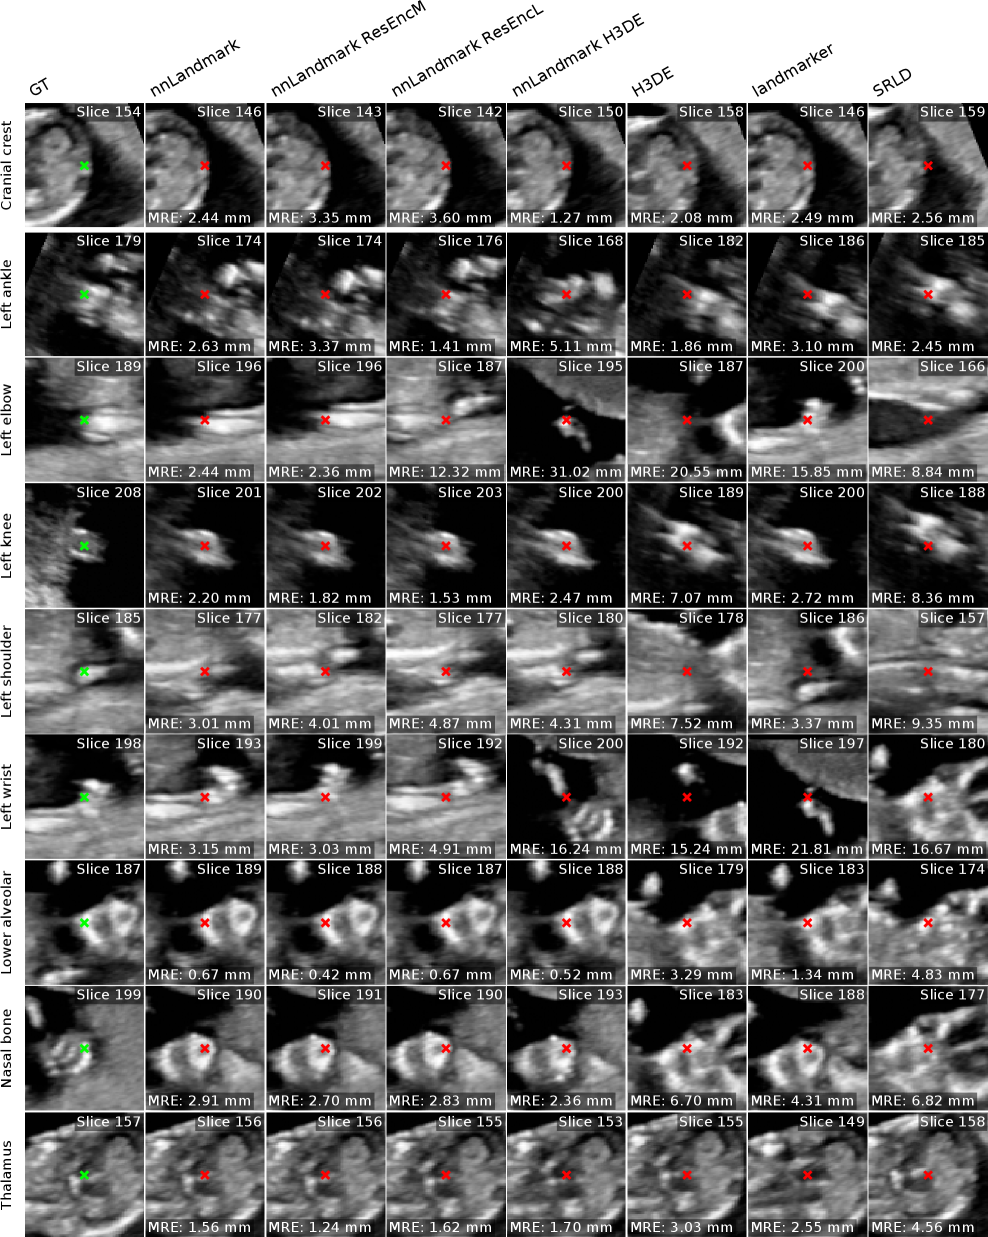

Randomly chosen example predictions for the nnLandmark ResEncM model for all datasets are shown in Figure 9. Visual examples for all methods are given in the Appendix F.